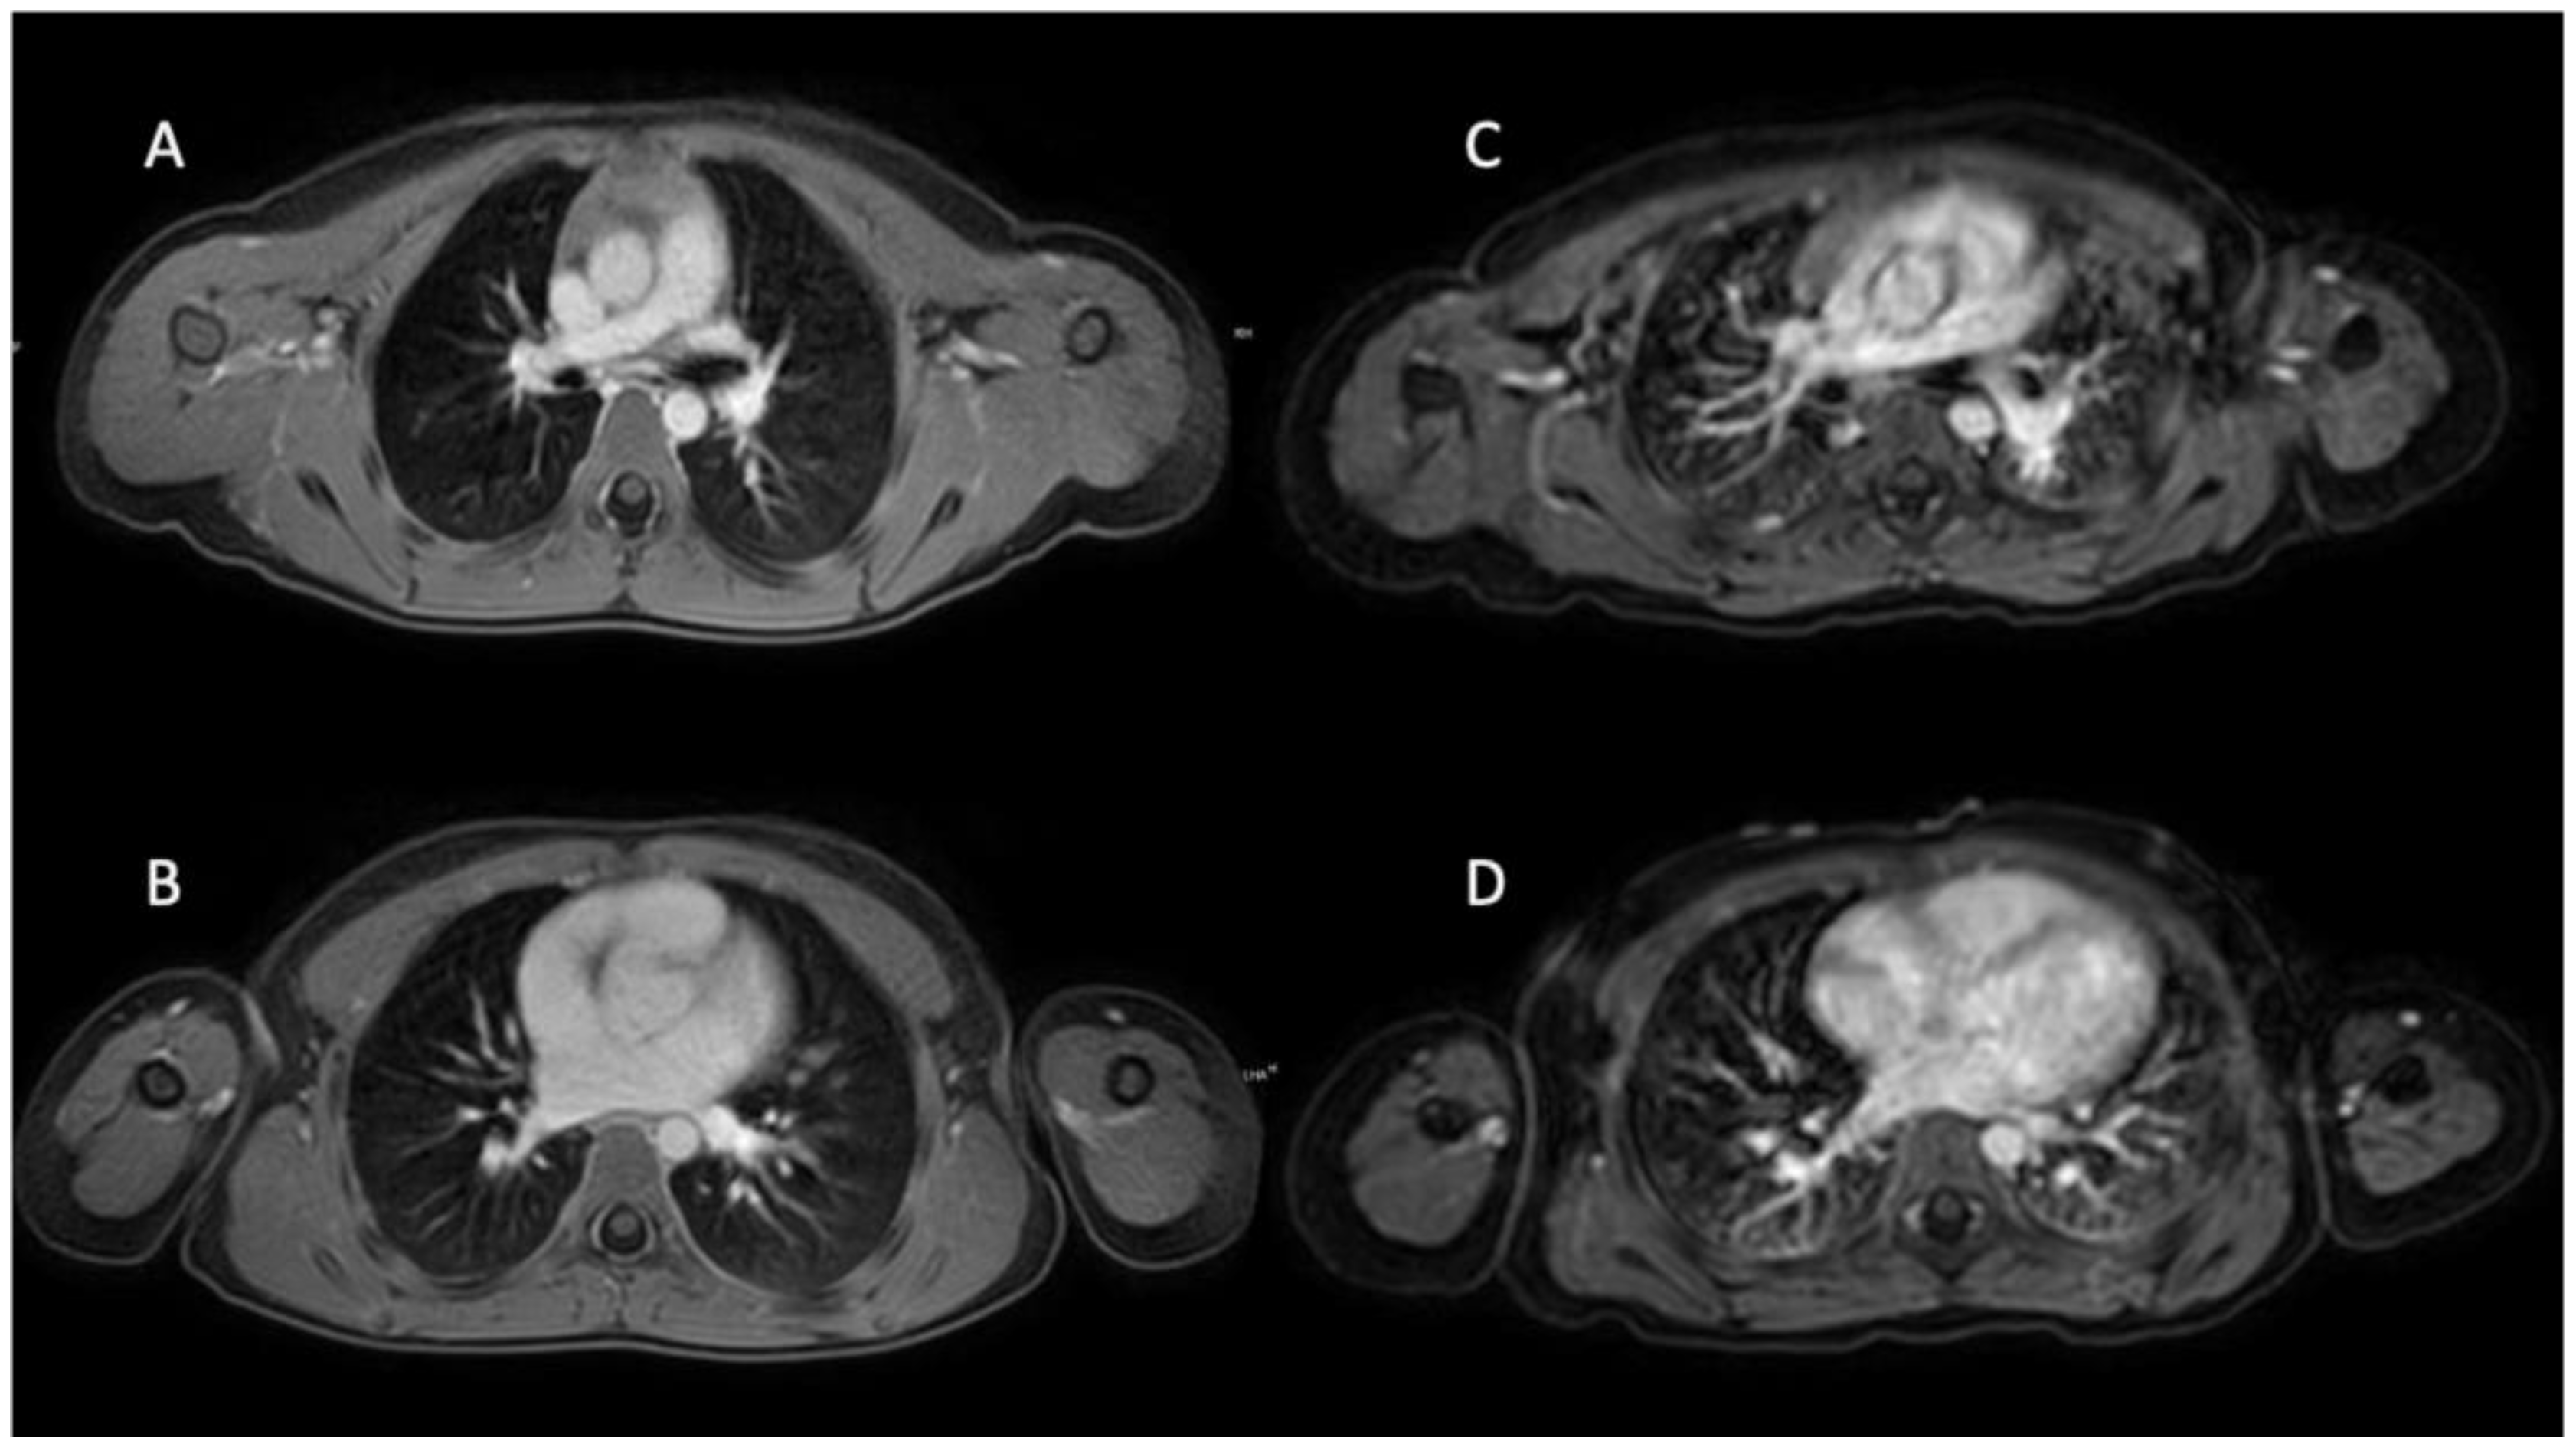

According to the results of Fleiss’ kappa analysis, the interobserver agreement ranged from substantial to almost perfect. For the VANE cohort, mean ϰ values across the parameters diagnostic image quality, presence of respiratory artifacts and depiction of pulmonary vessels reached 0.74. In the BH cohort, the corresponding mean ϰ was at 0.85. Detailed tables of reader agreement for each quality criterion are summarized in Table 4. Representative examples illustrating image quality from patients imaged with 3D T1w VANE mDIXON compared to those from the BH group are shown in Figure 3.

Figure 3.

Six-year-old girl with neuroblastoma undergoing 3D T1 VANE mDIXON in sedation (A,B). Four-year-old girl with rhabdomyosarcoma using conventional cartesian breath-hold T1w mDIXON under general anesthesia (C,D). Diagnostic image quality ratings on a 5-point Likert scale, with 5 being the best, provided by reader 1 (R1), reader 2 (R2) and reader 3 (R3); (A,B) R1: 4, R2: 5 and R3: 5, (C,D) R1: 3, R2: 3 and R3: 4.